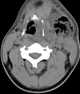

Neck infection